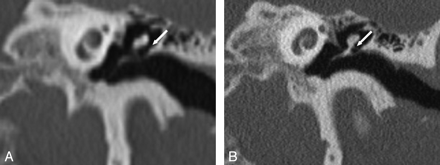

Temporal bone axial MPR, section thickness 0.8 mm, in both SST (A) and MSCT (B). The anterior mallear ligament (1), malleus head (2), incus body (3), and incudomallear articulation (4) can be seen clearly with both imaging techniques.